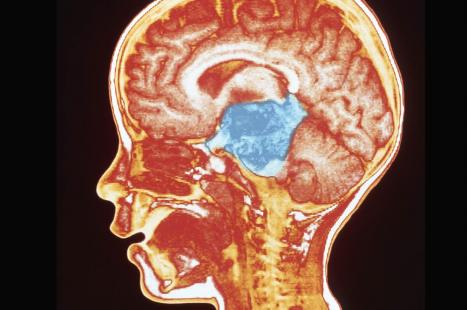

La tumeur survient chez des enfants âgés entre 4 à 9 ans. La tumeur touche une région difficile d’accès et à extraire chirurgicalement, avant d’infiltrer largement le tronc cérébral. Malgré la radiothérapie, la survie est en général de 9 mois, et moins de 1 % vivent plus longtemps que 5 ans.

Les chercheurs ont travaillé à partir de prélèvements anatomopathologiques provenant d’enfants des États-Unis et d’Europe. À l’aide d’un screening à haut débit, ils ont constaté que la famille des inhibiteurs de la déacétylase des histones était capable de ralentir la croissance cellulaire des gliomes. Des expériences complémentaires ont corroboré la piste des histones. « Toutes les routes mènent aux histones, a expliqué le Dr Monje. Nos résultats soutiennent l’idée que les modifications des histones sont les clefs de la compréhension et du traitement du GPDI. » Près de 80 % des tumeurs GPDI présenteraient une mutation spécifique génétique concernant les histones.